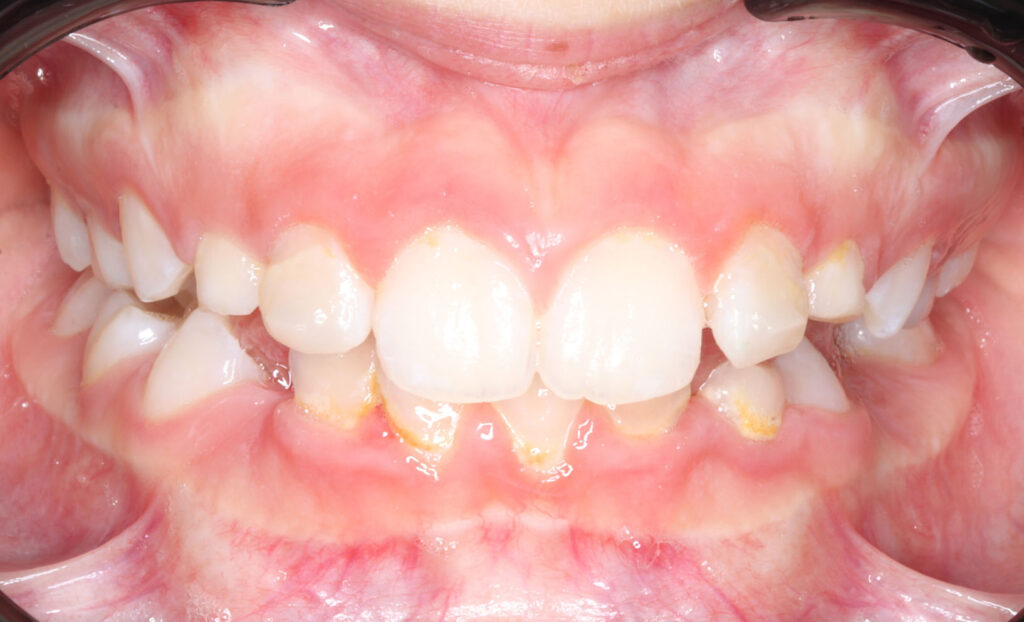

Case report of a 9-year-old female patient in the intermediate phase of mixed dentition. The patient presents with moderate upper and lower crowding, narrow arches, Class II molar relationship on the right side, premature loss of tooth 83, deviation of the lower midline to the right, deep bite, and a crossbite on the right side affecting only the deciduous dentition.

The goal of the treatment was to achieve transverse development of both arches, proclination of upper and lower incisors to correct the deep bite, and to create space for the blocked tooth.